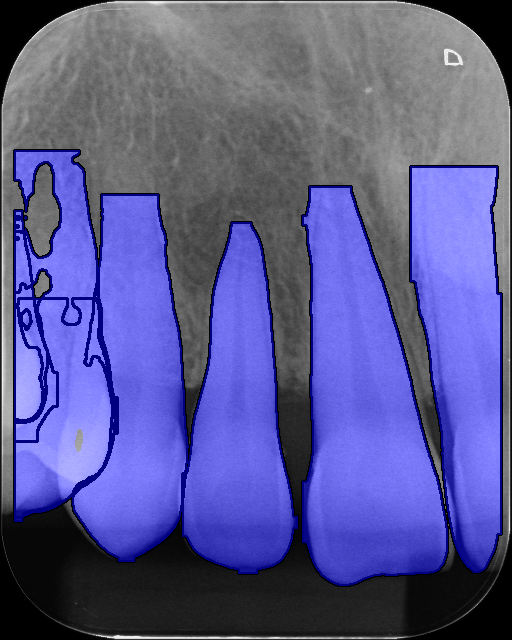

As a single trained segmentation model is to be used on our differing domain periapical dataset, which does not contain its own tooth segmentation labels, we primarily evaluated the performance qualitatively on our dataset and the cropped panoramic validation set. Additional training details and quantitative results on the auxiliary segmentation validation set are in A

During inference with the post-processing module, we intentionally tuned prediction stage hyperparameters to over-predict segmentation masks. We did this by setting the Intersection over Union (IoU) threshold to 0.70.7 and confidence threshold to 0.150.15, which predicts a large number of overlapping masks of varying quality and completeness. We then use Non-Maximum Merging (NMM) [44] with an IoU threshold of 0.10.1. This is done to combine the large number of poor quality predicted masks, that is produced by the model when qualitatively evaluated on our different domain distribution dataset, into a cohesive and higher quality tooth masks, as seen in Figure 3.

Refer to caption

(a) Before NMM

(b) After NMM

Figure 3: Images containing predicted segmentation mask overlays, for Image 1, where (a) is before NMM and (b) is after NMM.

When segmenting the teeth in the image, we expect occasional false positive predictions from the instance segmentation model. This in turn, produces multiple redundant segmentation mask orientation angles, which are filtered out during post processing.